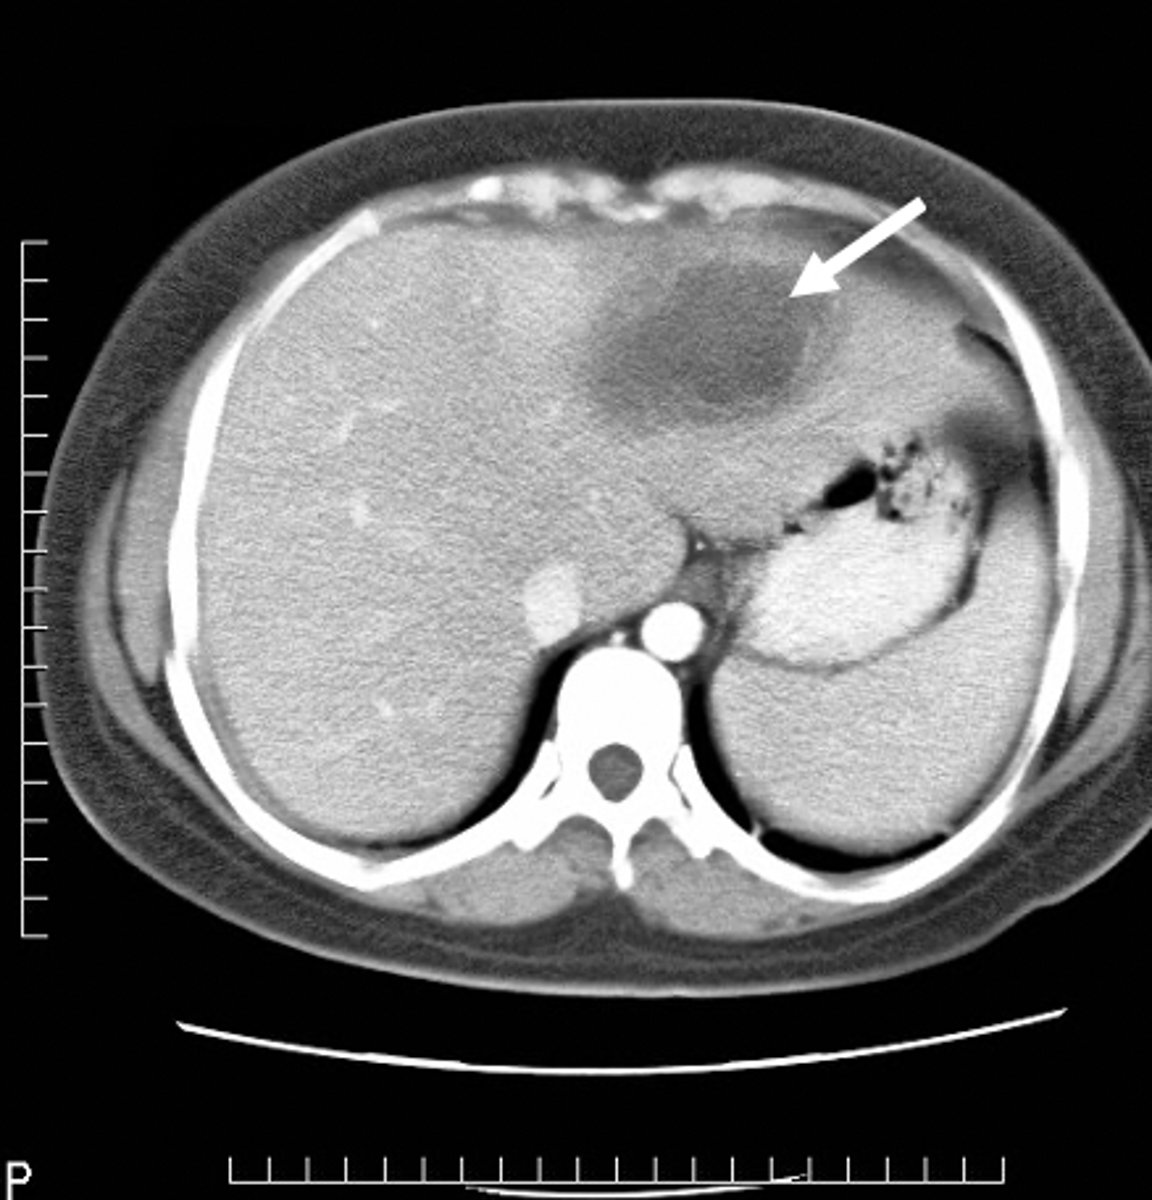

spleen

most highly vascular organ, most injured organ in blunt trauma

CT is diagnostic study of choice

Tx: mostly non-surgical

splenic laceration

hemorrhage and hematoma present, dark fluid is blood surrounding spleen